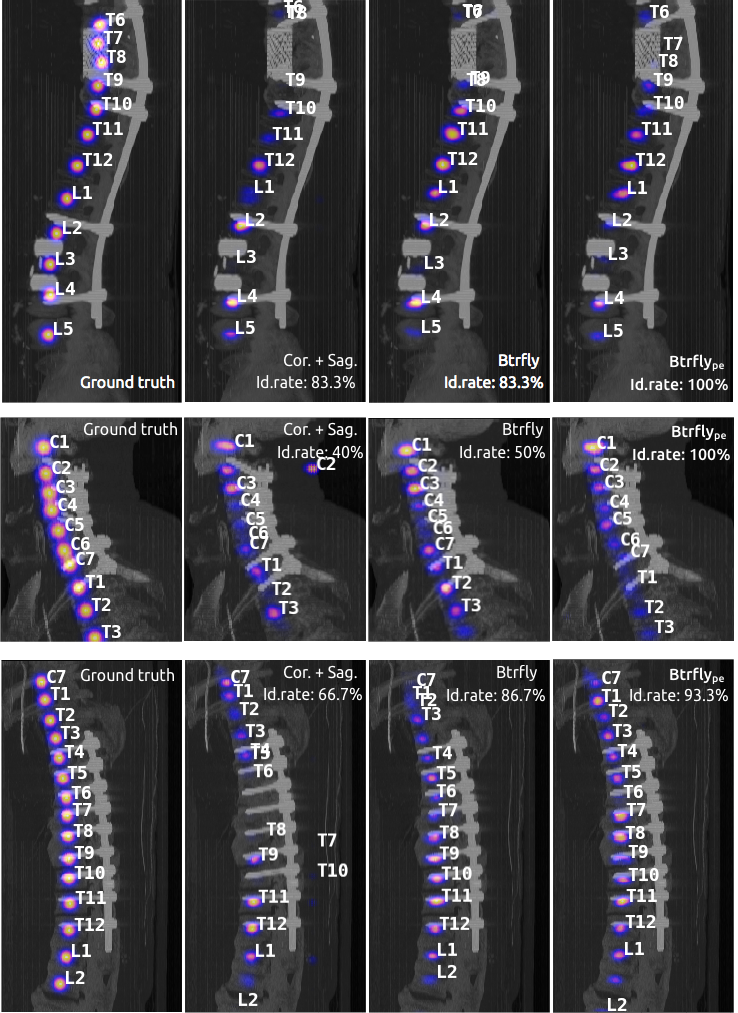

Evaluation & discussion. For evaluating the performance of our network with prior work, we use two metrics defined in [2] namely, the identification rates (id. rate, in %) and localisation distances (d & d, in ). We report the measures in Table 1. It lists the performance of three variants of our network and compares them with several recent approaches. We address three main questions through our experiments: (1) Why the butterfly shape? Compared to Cor.+Sag. nets, performance improves with the Btrfly net. This is because the combination of views causes the predictions of the Btrfly net to be spatially consistent across views. We also observe a 6% improvement in the id.rate over a naive 3D FCN (DI2IN). (2) Why the adversarial prior-encoding? In addition to the advantages of the Btrfly net, the Btrfly net possesses adversarially encoded spatial distribution of the vertebrae. This results in about a 4% increase in the id. rate. Compared to the prior work, Btrfly net achieves state-of-art measures in both the metrics, and it does so by being a single network trained end-to-end. (cf. Fig. 4) (3) Relation to latent-space learning? EB- is more flexible than the AEs in [4, 5] as it learns from scratch and converges to a latent manifold best representing the true as well as generated data. The reconstruction capability of the AE for a generated sample is of interest. Using the output of the AE instead of Btrfly, we achieve an id.rate of 75% with a d of , indicating the AEs’ capability of transferring the learning from true to contrastive samples.